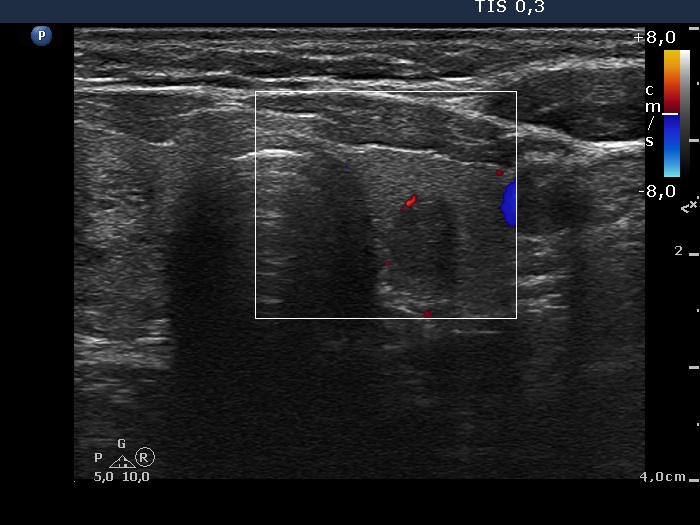

Left lobe, transverse scan, color Doppler mode. The vascularization is not specific.